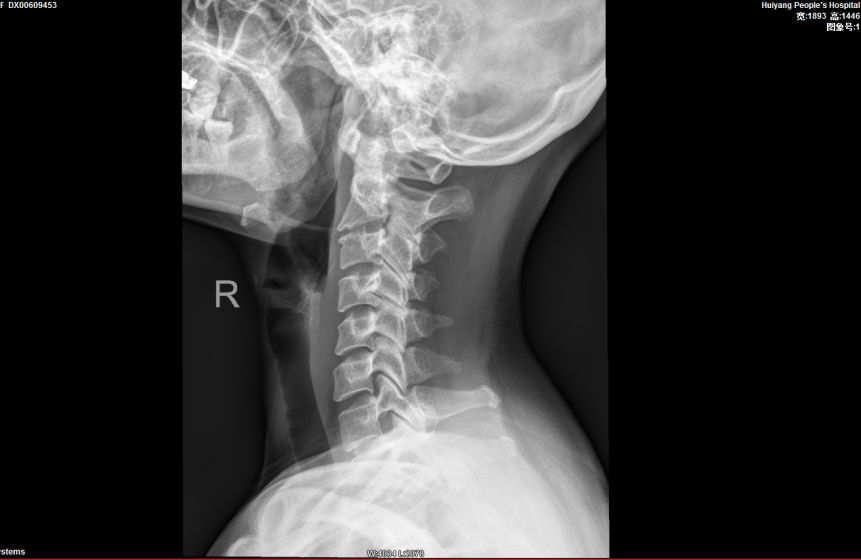

▲頸椎生理曲度變直,骨質增生退變

完善相關檢查後(hòu), 報告提示患者的頸椎生理曲度變直,序列如常。C2-7椎體邊緣可見不同程度骨質變尖、突起(qǐ)。C2/3椎間隙明顯變窄,呈前窄後(hòu)寬改變;餘椎間隙未見明顯變窄。項韌帶未見鈣化。寰樞關節開(kāi)口位見雙側不對(duì)稱,左側較右側爲寬(左側6mm,右側3mm),關節面(miàn)光整,寰椎、樞椎骨質未見明顯異常。周圍軟組織未見異常密度。